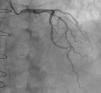

At five-year follow-up after transplantation, the routine coronary angiography (Figure 1) showed progression of the two mid LAD stenoses (50-70%) and revealed that the LIMA–LAD graft was no longer patent.